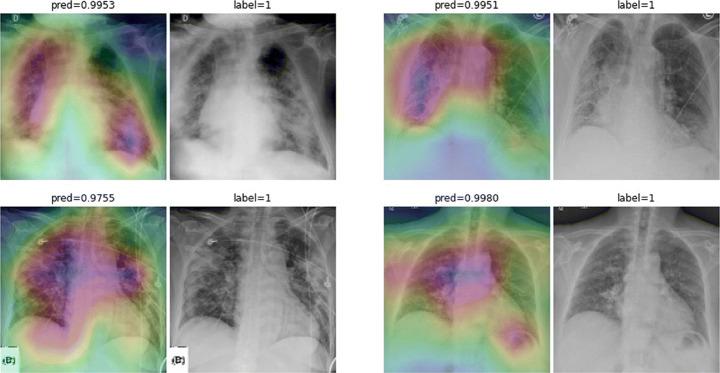

One of the primary clinical observations for screening the novel coronavirus is capturing a chest x-ray image. In most patients, a chest x-ray contains abnormalities, such as consolidation, resulting from COVID-19 viral pneumonia. In this study, research is conducted on efficiently detecting imaging features of this type of pneumonia using deep convolutional neural networks in a large dataset. It is demonstrated that simple models, alongside the majority of pretrained networks in the literature, focus on irrelevant features for decision-making. In this paper, numerous chest x-ray images from several sources are collected, and one of the largest publicly accessible datasets is prepared. Finally, using the transfer learning paradigm, the well-known CheXNet model is utilized to develop COVID-CXNet. This powerful model is capable of detecting the novel coronavirus pneumonia based on relevant and meaningful features with precise localization. COVID-CXNet is a step towards a fully automated and robust COVID-19 detection system.

筛查新型冠状病毒的主要临床观察方法之一是拍摄胸部X光图像。在大多数患者中,胸部X光显示出由COVID-19病毒性肺炎引起的异常,如实变。在本研究中,我们利用深度卷积神经网络在一个大型数据集中对这种类型肺炎的成像特征进行高效检测。结果表明,简单模型以及文献中的大多数预训练网络都关注于与决策无关的特征。本文收集了来自多个来源的大量胸部X光图像,并准备了一个最大的公开可用数据集。最后,使用迁移学习范式,利用著名的CheXNet模型开发了COVID-CXNet。这个强大的模型能够基于相关且有意义的特征精确地定位检测新型冠状病毒肺炎。COVID-CXNet朝着全自动且强大的COVID-19检测系统迈出了一步。